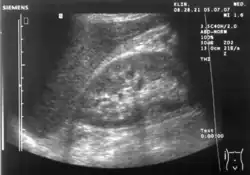

Échographie abdominale

L'échographie abdominale est une forme d'échographie médicale (application médicale de la technologie des ultrasons) permettant de visualiser les structures anatomiques abdominales. Il utilise la transmission et la réflexion des ondes ultrasonores pour visualiser les organes internes à travers la paroi abdominale (à l'aide de gel, qui aide à la transmission des ondes sonores). Pour cette raison, la procédure est également appelée échographie transabdominale, contrairement à l'échographie endoscopique, cette dernière combinant l'échographie et l'endoscopie en visualisant les structures internes à l'intérieur des organes creux. Les examens échographiques abdominaux sont réalisés par des gastroentérologues ou autres spécialistes en médecine interne, des radiologues ou des échographistes formés à cette procédure.

L'échographie abdominale peut être utilisée pour diagnostiquer des anomalies dans divers organes internes, tels que les reins[1], le foie, la vésicule biliaire, le pancréas, la rate et l'aorte abdominale . Si l'échographie Doppler est ajoutée, le flux sanguin à l'intérieur des vaisseaux sanguins peut également être évalué (par exemple, pour rechercher une sténose de l'artère rénale ). Il est couramment utilisé pour examiner l'utérus et le fœtus pendant la grossesse ; c'est ce qu'on appelle l'échographie obstétricale[2],[3]. L'échographie abdominale est couramment utilisée dans le cadre de douleurs abdominales ou d'un abdomen aigu (syndrome douloureux abdominal soudain et/ou sévère dans lequel une intervention chirurgicale peut être nécessaire), dans lequel elle peut diagnostiquer une appendicite ou une cholécystite. L'échographie peut également être utilisée en cas de suspicion d'hypertrophie d'un ou de plusieurs organes, comme celle utilisée dans le dépistage de l'anévrisme de l'aorte abdominale, l'investigation de la splénomégalie ou la rétention urinaire.